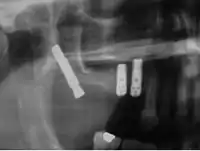

Los implantes cigomáticos deben ser colocados por equipos expertos de cirujanos maxilofaciales. Dichos implantes de se colocan bajo anestesia general siempre después de un completo examen quirúrgico y un estudio oral integral completo, que debe incluir modelos dentales del paciente, rayos X y fotos dentales.